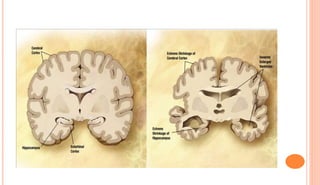

MICROSCOPIC EXAMINATION